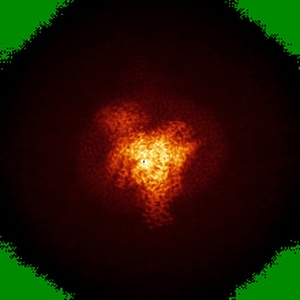

SR17018-bound mu-opioid receptor-Gi complex

Single-particle3.2 Å

Sample: fentanyl bound mu-opioid receptor-G protein complex